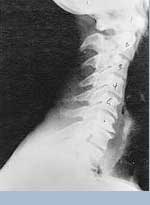

This is a side x-ray view of the neck. As with all the pictures you will see on this page, the patient is looking to the right of the screen, so you are viewing the right side of their neck. We will call this picture a "near normal" spine. Compare this spine with the ones you will see below on this page. Notice the normal forward curve of the neck. This curve helps absorb shock. Notice how each of the disc spaces between C2 (second bone in neck) and C7 are thick and even, this again is normal. Also notice how the front portions (right on the x-ray) of each of the vertebrae (called the 'body' of the vertebrae) are fairly square with clear and well defined borders. This type of arrangement is normal in the neck. Normal vertebrae in other parts of the spine also have similar characteristics to what we see here. When subluxations occur and are left uncorrected, ongoing relentless changes occur that result in damage to the structure and function of the spine along with nerve damage and the resulting problems caused from improper nerve supply.